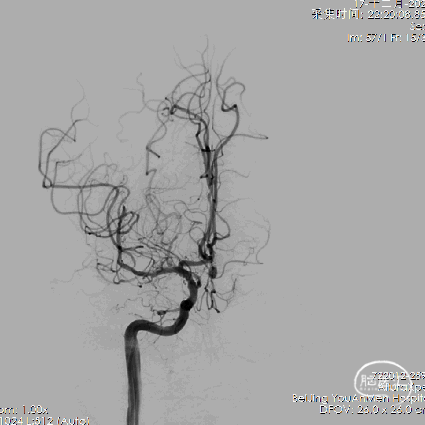

1、右侧颈内动脉造影提示双侧大脑前动脉显影,前交通动脉可见动脉瘤。

4、工作位测量:瘤颈长约3.94mm,瘤体大小约9.09×7.40mm,主瘤体上可见三个子瘤大小分别为:3.84×2.43mm、3.09×2.54mm、3.39×2.44mm。

5、双微导管分区填塞动脉瘤。

6、填圈期间动态造影监测左侧大脑前动脉血流有无影响。

7、在瘤颈处可见可疑血栓影。

8、左侧大脑前动脉血流变慢。

9、动脉给予替罗非班后,左侧大脑前动脉血流未见好转。

10、将瘤颈口的微导管撤出后,左侧大脑前动脉血流较前略有好转。

11、反复造影观察后血流速度仍然减慢,造影见少量弹簧圈突入前交通动脉。

12、超选左侧大脑前动脉跟进微管,可见路径迂曲。

13、支架置入后左侧大脑前动脉血流好转。

14、栓塞后造影。

栓塞后正位造影